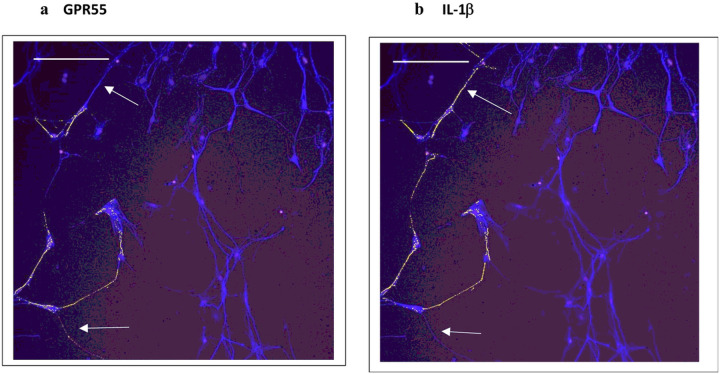

Based on concepts revealed from previous studies of KLS-13019-mediated inhibition of paclitaxel-induced inflammation (ref. Brenneman et al., 2022), the following inflammatory mediators were chosen to monitor effects of GPR55 siRNA: GPR55, NLRP3 and IL-1b. In the present study, the entire focus was on neuronal imaging as determined by beta-3 tubulin immunofluorescence. In Fig. 1, immunofluorescence spots of GPR55 and NLRP3 are shown indicating that these two measures of inflammation tracked together in the same location in GPR55-positive neurons. In all GPR55-positive neurons, NLRP3 immunoreactive (IR) spots were also observed. Most DRG neurons were not IR-positive for either marker, as only 25% of the neurons were positive for GPR55. Because an increase in NLRP3 was suggestive of an activation of the inflammasome − 3 complex, IL-1beta was also surveyed for IR spots in the DRG cultures. As shown in Fig. 2, the IR spot distribution in DRG neurons was compared for GPR55 and IL-1b. As in the observation made in Fig. 1, most neurons were not positive for either GPR55- or IL-1b. However, in all cases, neurons that were positive for GPR55 were also positive for IL-1b, although the distribution within the neurons was often slightly different, with IL-1b being more prevalent. To facilitate comparisons between the various analytes, changes were expressed as a percent of control. In Table 3, the control levels per neuron are presented for each analyte as determined by high content analysis of immunoreactive spots.